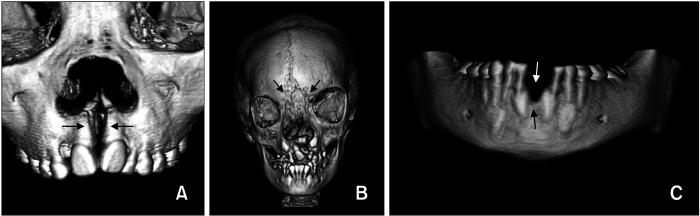

The three most common types were #7 cleft, followed by #0 cleft and #14 cleft. There was no difference between the frequency of male and female. Patients with #0 cleft exhibited nasal deformity, bony defect, and missing teeth in the premaxilla, midline cleft lip, and eye problems. A patient with #3 cleft (unilateral type) exhibited bilateral cleft lip and alveolus. All patients with #4 cleft were the bilateral type, including a combination of #3 and #4 clefts, and had multiple missing teeth. A patient with #5 cleft (unilateral type) had a posterior openbite. In patients with #7 cleft, the unilateral type was more prevalent than the bilateral type (87.0% vs. 13.0%, p < 0.001). Sixteen patients showed hemifacial microsomia (HFM), Goldenhar syndrome, and unilateral cleft lip and palate (UCLP). There was a significant match in the side involvement of #7 cleft and HFM (87.5%, < 0.01). Patients with #14 cleft had plagiocephaly, UCLP, or hyperterorbitism. A patient with #30 cleft exhibited tongue tie and missing tooth.

最常见的三种类型依次为7号裂,其次是0号裂和14号裂。男女发病率无差异。0号裂患者表现为鼻畸形、骨缺损、上颌前部牙齿缺失、正中唇裂和眼部问题。1例3号裂(单侧型)患者表现为双侧唇裂和牙槽突裂。所有4号裂患者均为双侧型,包括3号裂和4号裂的组合,且有多颗牙齿缺失。1例5号裂(单侧型)患者有后牙开 。7号裂患者中,单侧型比双侧型更常见(87.0%对13.0%,p<0.001)。16例患者表现为半侧颜面短小畸形(HFM)、Goldenhar综合征和单侧唇腭裂(UCLP)。7号裂与HFM的患侧有显著匹配(87.5%,<0.01)。14号裂患者有斜头畸形、UCLP或眶距增宽。1例30号裂患者表现为舌系带过短和牙齿缺失。